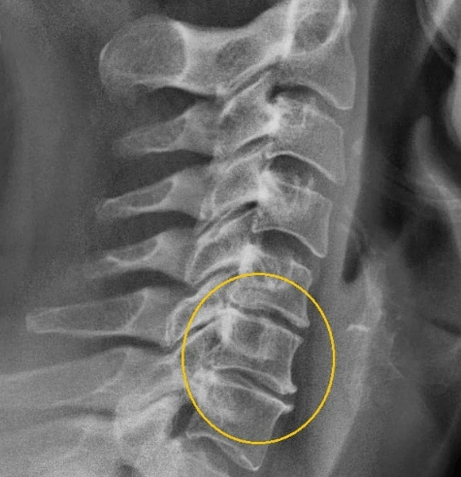

At this stage, the protrusion of the vertebrates began, the intervertebral cracks have tightened, the fiber fibrous fiber of the collagen disc is destroyed. There are evident painful symptoms of nature in one point due to the compression of the nerve trunks, which intensify during the neck movements and the curves of the head. Here you can already suspect cervical osteochondrosis, whose symptoms in the second stadium are as follows:

Phase III

The fibrous ring on the disc is destroyed, hernias are formed. In the third phase, there is a deformation of the spine, the movement and dislocation of the vertebrae due to their weak fixation. The symptoms are as follows:

- Intensive and acute pains in the neck, collar area, cardiac area;

- The sensitivity of the scalp on the back of the head, in the shoulder region, in the hands, until the complete absence of;

- hernia of the cervical column;